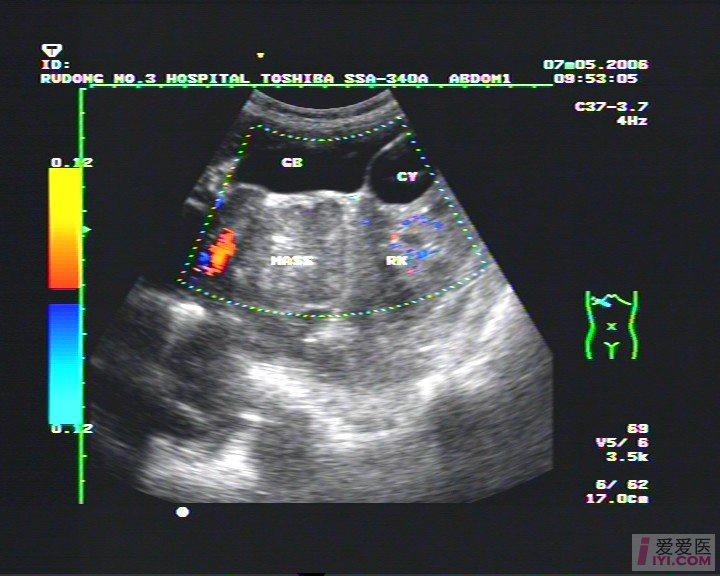

【即时求助】肝肾隐窝处不均质肿块 - 超声医学讨论版 - 爱爱医医学

图片尺寸720x576![【讨论】肝肾隐窝占位病变鉴别 [病例帖]](https://i.ecywang.com/upload/1/img0.baidu.com/it/u=3897215977,1901904261&fm=253&fmt=auto&app=138&f=JPEG?w=375&h=500)